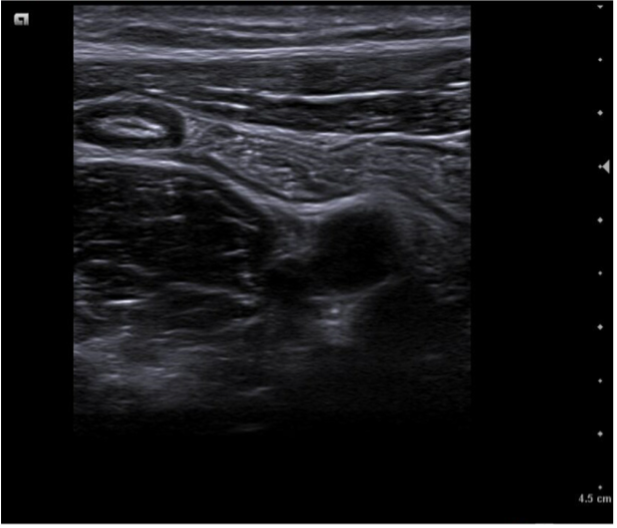

Caso 2. Asa intestinal fija con edema de pared por posible apendicitis o ileitis. Corte transversal con signo del donut.